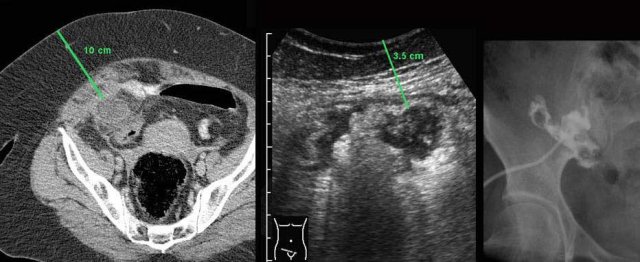

This patient had a large appendiceal abscess, walled-off by ileum and cecum.

A small window (arrow) allowed US-guided puncture.

Insertion of the drain over a guidewire was done under fluoroscopic control.

In this obese patient, drainage with the US probe using compression, allows the needle to approach the abscess closely.

Note that compression here reduced the distance skin-to-abscess from10 to 3.5 cm.